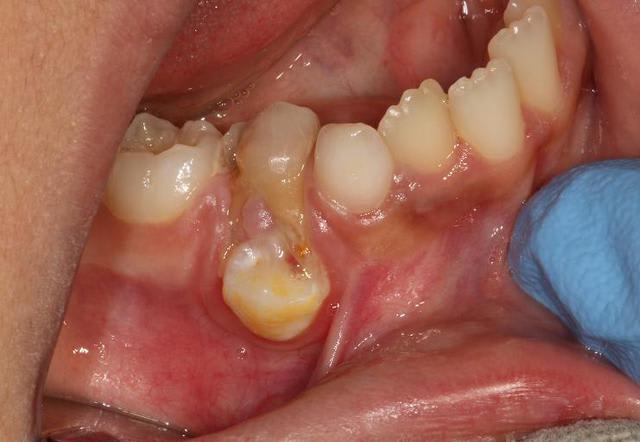

Patient de 51 ans, très gentil, très souriant (!!), je l'ai vu début décembre en urgence pour extraction de la 24 (mobilité 72) et comme je l'ai revu hier j'en ai profité pour prendre des photos, ce n'est pas le champion, mais je l'ai jugé digne de concourir :

Deuxième photo après 3/4h de détartrage, pas encore fait de surfaçage et de polissage, je voyais la gencive redevenir rose au fur et à mesure, il ne mérite pas une gencive si costaud :-)

Désolé les photos ne sont pas dans le bon ordre.